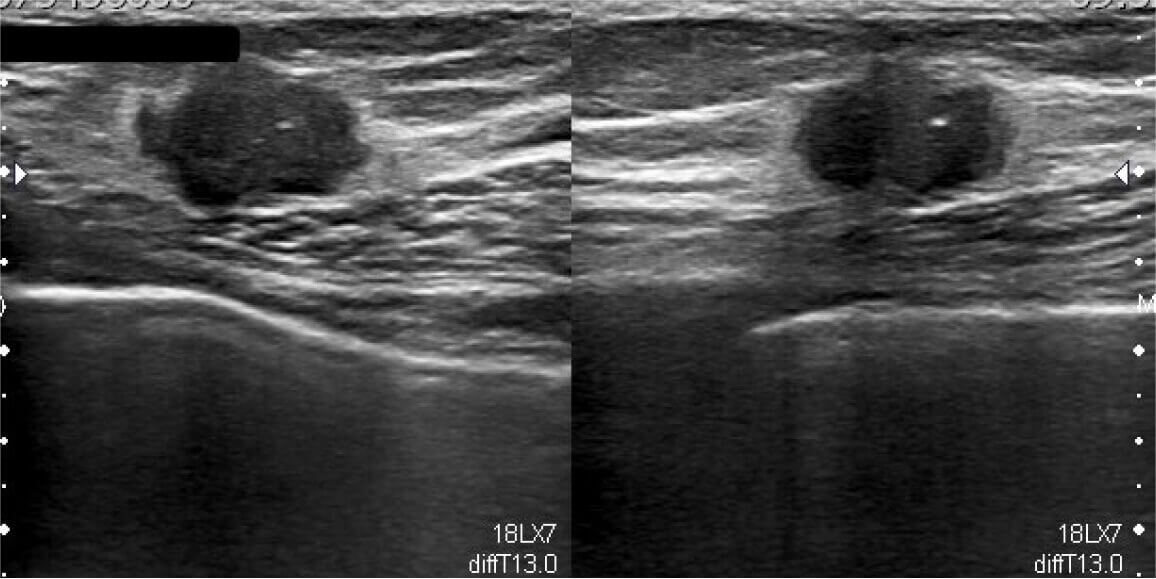

На консультацию к пациентке были приглашены вы в качестве врача-онколога. Вы принимаете решение о проведении повторного ультразвукового исследования и маммографии. По результатам обследования врачи‑диагносты сходятся во мнении о злокачественной природе выявленного образования в молочной железе (BI‑RADS 4).

Рис. 3 — фрагмент с результатами ультразвукового исследования молочных желез. В отличие от предыдущего результата, новообразование характеризуется бугристостью, нечеткими контурами и гетерогенностью, что может соответствовать злокачественному новообразованию (BI-RADS 4).